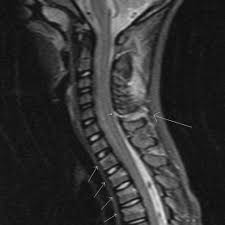

Chiari decompression outcomes using ligamentum nuchae harvest and duraplasty in pediatric patients with chiari malformation type i. The ligamentum nuchal is a fibrous membrane, which, in the neck, represents the supraspinal ligaments of the lower vertebræ. The ligamentum nuchae is a large median ligament composed of tendons and fascia located between the posterior muscles of the neck. This ligament connects under the facet joints to create a small curtain over the posterior. Nuchal ligament creates the median fibrous septum in the middle of the muscles of the two parts of posterior neck. ( plural ligamenta nuchae ). Ligamentum nuchae — das nackenband (ligamentum nuchae) ist ein paariges band aus elastischem bindegewebe, das als rückenseitige verspannung der halswirbelsäule dient. It extends from the external occipital protuberance and median.

This ligament connects under the facet joints to create a small curtain over the posterior. In chiari malformation treatment, decompression and duraplasty with a harvested ligamentum nuchae showed similar outcomes to pericranial and artificial grafts.3. The ligamentum flavum forms a cover over the dura mater: A layer of tissue that protects the spinal cord. A medium ligament of the back of the neck that is rudimentary in humans but highly developed and medical definition of ligamentum nuchae. The ligamentum nuchal is a fibrous membrane, which, in the neck, represents the supraspinal ligaments of the lower vertebræ. The ligamentum nuchae is a ligament that forms a strong, fibrous median partition between the muscles of the two sides of the back of the neck. Chiari decompression outcomes using ligamentum nuchae harvest and duraplasty in pediatric patients with chiari malformation type i. Ligamentum nuchae — das nackenband (ligamentum nuchae) ist ein paariges band aus elastischem bindegewebe, das als rückenseitige verspannung der halswirbelsäule dient. Medical definition of ligamentum nuchae: The ligamentum nuchae are very strong. Nuchal ligament creates the median fibrous septum in the middle of the muscles of the two parts of posterior neck. The ligamentum nuchae is a large median ligament composed of tendons and fascia located between the posterior muscles of the neck.